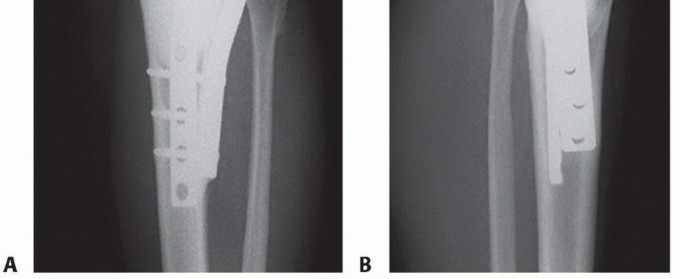

الكشط والعلاج المساعد (Curettage and Adjuvant Therapy):

تُستخدم عادة لأورام العظام الحميدة، حيث يتم كشط الورم من داخل العظم، ثم يتم استخدام مواد مساعدة مثل الفينول أو النيتروجين السائل أو الكي الكهربائي لتدمير أي خلايا ورمية متبقية.

5. العلاج بالتبريد (Cryoablation): النهج الثوري

يُعد العلاج بالتبريد، خاصةً بتقنية الصب المباشر بالنيتروجين السائل، ثورة حقيقية في علاج أورام العظام، حيث يقدم بديلاً فعالاً وآمنًا للجراحات الكبرى، مع الحفاظ على الطرف المصاب ووظيفته. يعتمد هذا النهج على تدمير الخلايا السرطانية عن طريق تعريضها لدرجات حرارة منخفضة جدًا، مما يؤدي إلى تجميدها وموتها.

- حفظ الأطراف: يقلل بشكل كبير من الحاجة إلى الجراحات الواسعة أو البتر.

- طفيف التوغل: يتطلب شقوقًا صغيرة جدًا، مما يقلل من فقدان الدم والألم بعد الجراحة.

- تعافٍ أسرع: فترة تعافٍ أقصر مقارنة بالجراحة التقليدية.

- ألم أقل: عادة ما يكون الألم بعد الإجراء أقل حدة.

- نتائج وظيفية ممتازة: يحافظ على وظيفة الطرف المصاب ومظهره.

- فعالية عالية: فعال في تدمير مجموعة واسعة من أورام العظام الحميدة والخبيثة.

- استهداف دقيق: يسمح بالتحكم الدقيق في منطقة التجميد لحماية الأنسجة السليمة.

يُعتبر الأستاذ الدكتور محمد هطيف ، أستاذ جراحة العظام في جامعة صنعاء، رائدًا في تطبيق تقنية الصب المباشر بالنيتروجين السائل في اليمن. بخبرته التي تزيد عن 20 عامًا في جراحة العظام والتعامل مع حالات أورام العظام المعقدة، يمتلك الدكتور هطيف فهمًا عميقًا لتشريح العظام وعلم الأورام، مما يمكنه من إجراء هذه التقنية بدقة متناهية. يحرص الدكتور هطيف على استخدام أحدث التقنيات التشخيصية والعلاجية، بما في ذلك الميكروسكوب الجراحي وتنظير المفاصل 4K وجراحات استبدال المفاصل، لتقديم أفضل رعاية ممكنة لمرضاه، مع التزامه الصارم بمبادئ الأمانة الطبية.

تقنية الصب المباشر بالنيتروجين السائل: تفاصيل الإجراء

تعتبر تقنية الصب المباشر بالنيتروجين السائل (Direct Pouring Liquid Nitrogen Technique) في العلاج بالتبريد لأورام العظام من التقنيات المتقدمة التي تتطلب دقة عالية وخبرة جراحية متخصصة. يفضل الأستاذ الدكتور محمد هطيف هذه التقنية نظرًا لفعاليتها في تحقيق تجميد عميق وشامل للورم، مع الحفاظ على الأنسجة السليمة المحيطة.